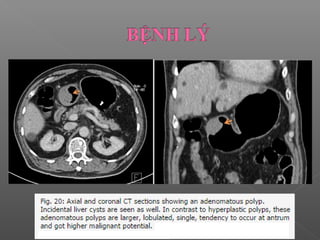

 Polyp dạng u tuyến (adenomatous polyp)

 Ít gặp hơn, 40% chuyển thành ác tính.

 Kích thước lớn hơn.

 Có cuống với bề mặt thùy múi.

 Nằm ở hang vị

 Polyp dạngu tuyến (adenomatous polyp)  Ít gặp hơn, 40% chuyển thành ác tính.  Kích thước lớn hơn.  Có cuống với bề mặt thùy múi.  Nằm ở hang vị